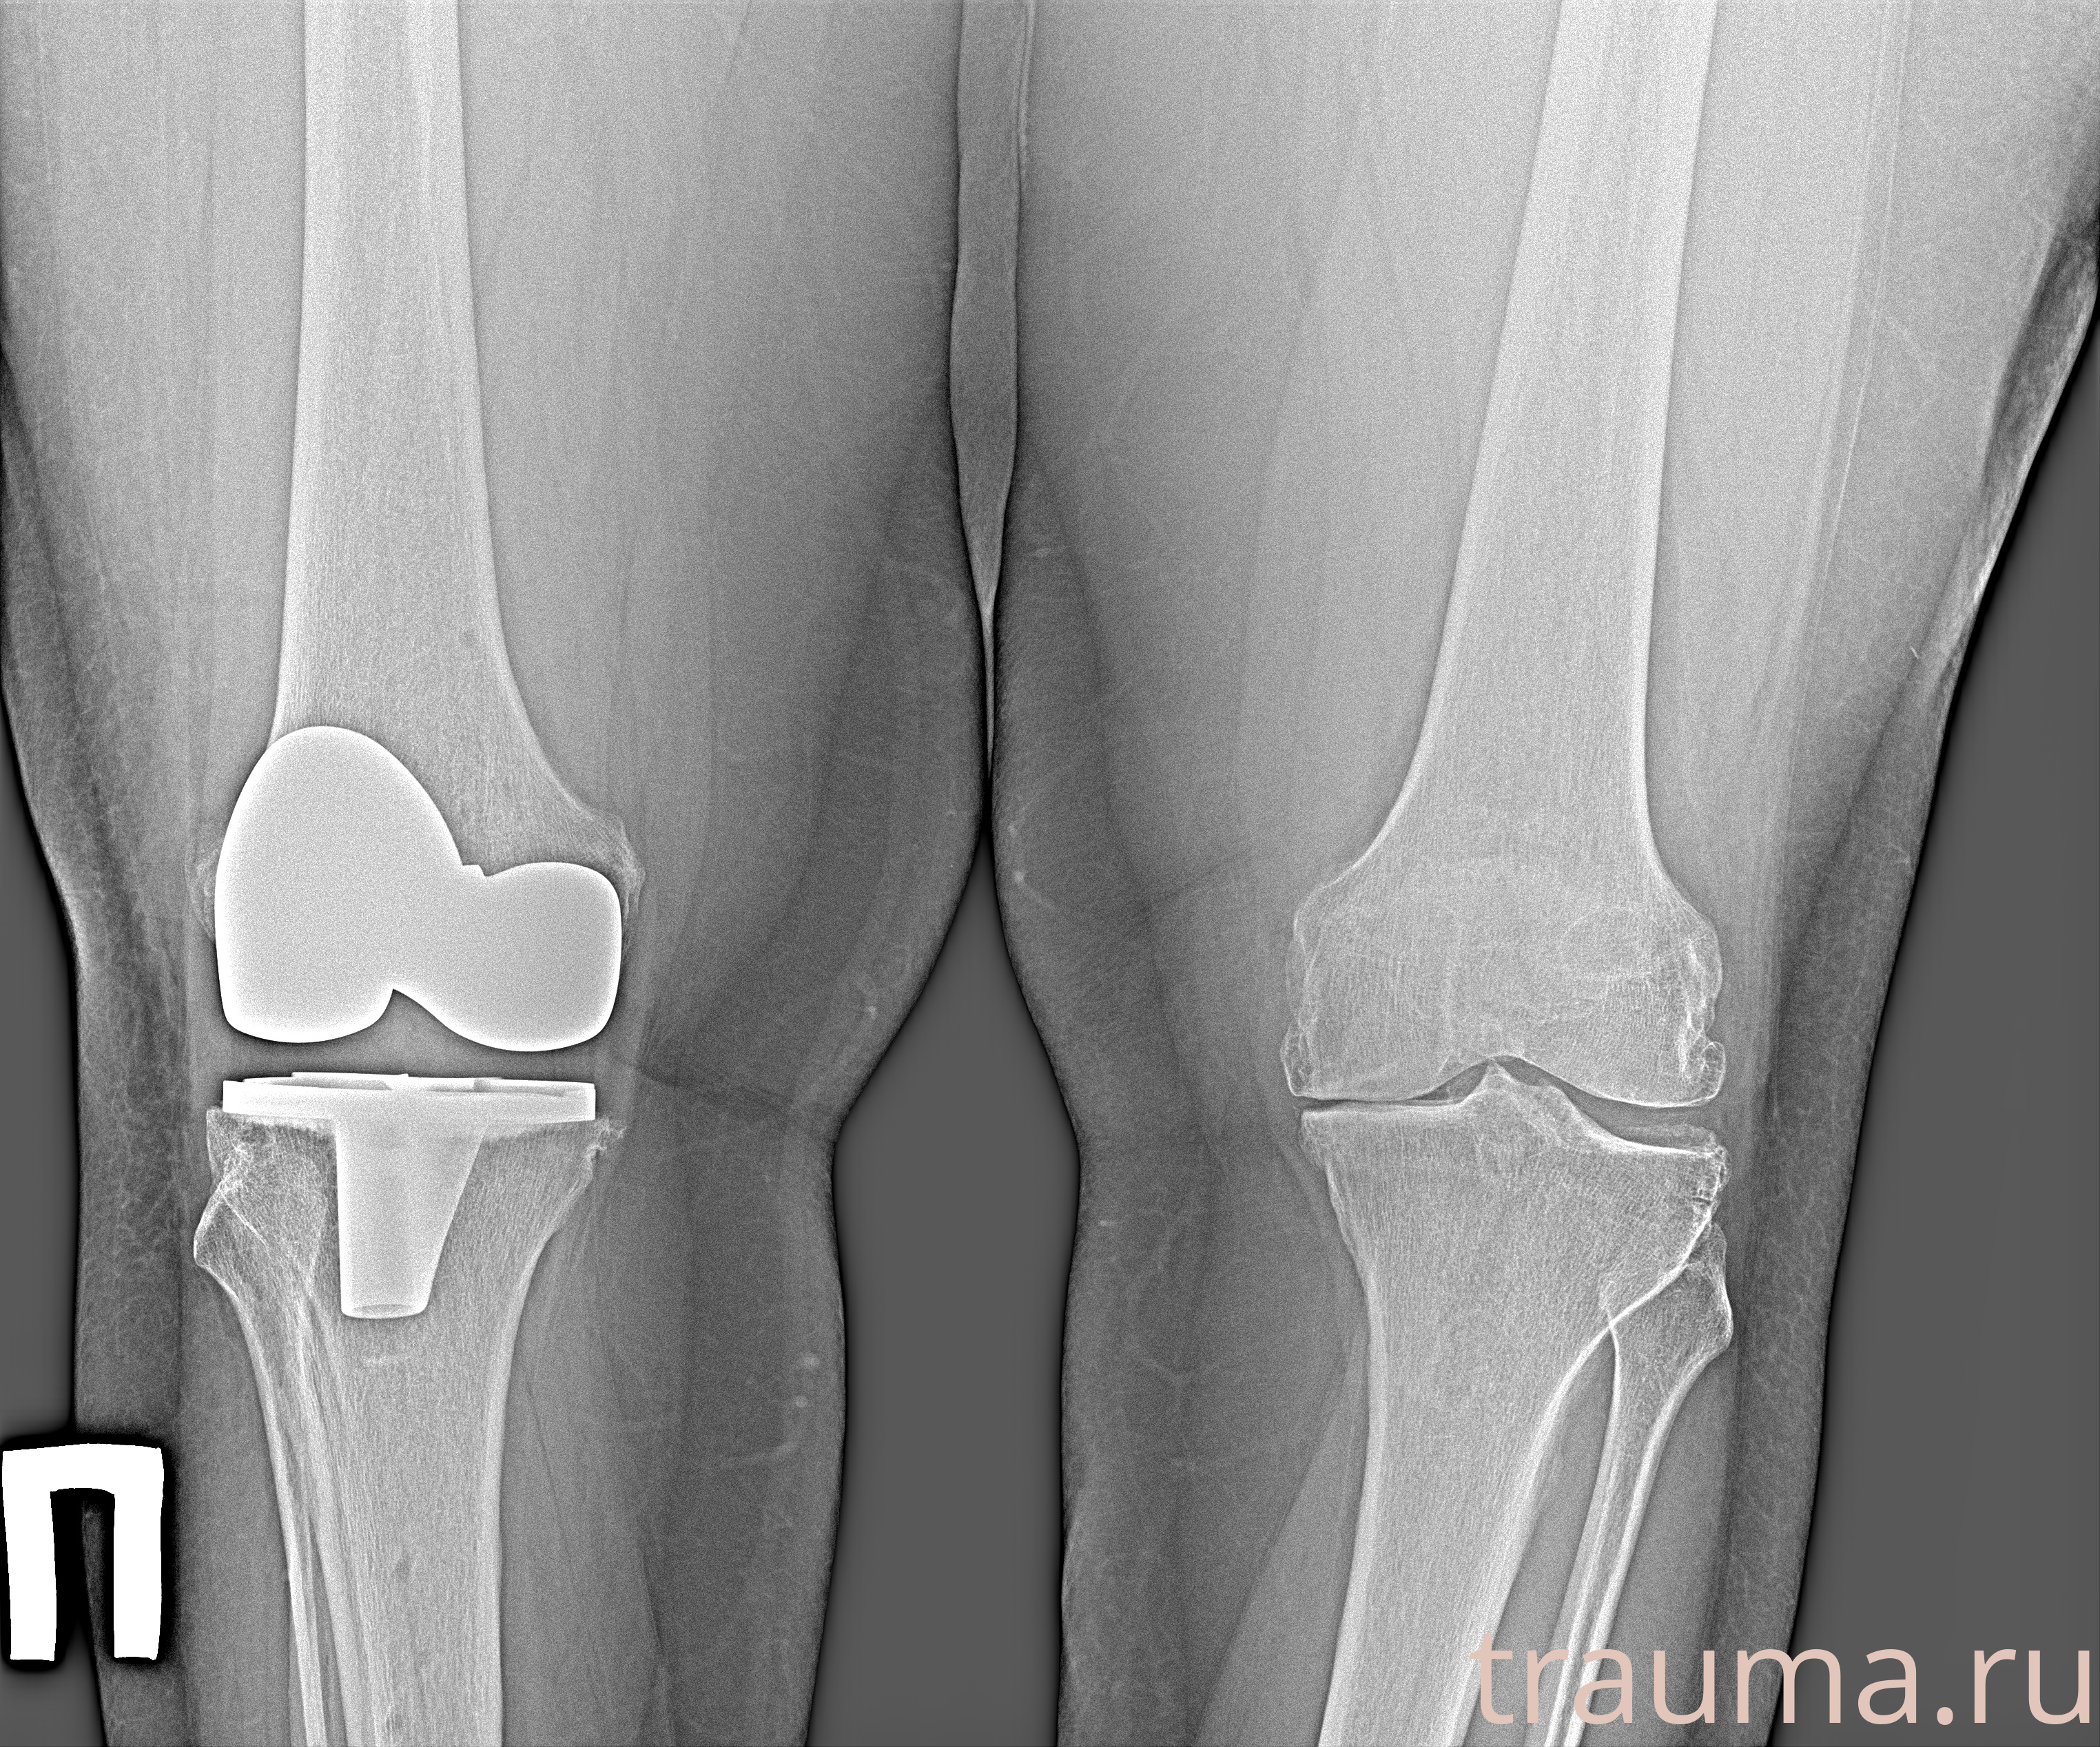

Рентгенограммы

Рентген на дому: по вашему адресу приезжает врач-рентгенолог, травматолог-ортопед с мобильным рентгеновским аппаратом, проводит диагностику травмы или заболевания, делает необходимые рентгенограммы, дает рекомендации по дальнейшему лечению. Получить качественные снимки в домашних условиях возможно благодаря уникальной методике, разработанной МосРентген Центром для института  Склифосовского